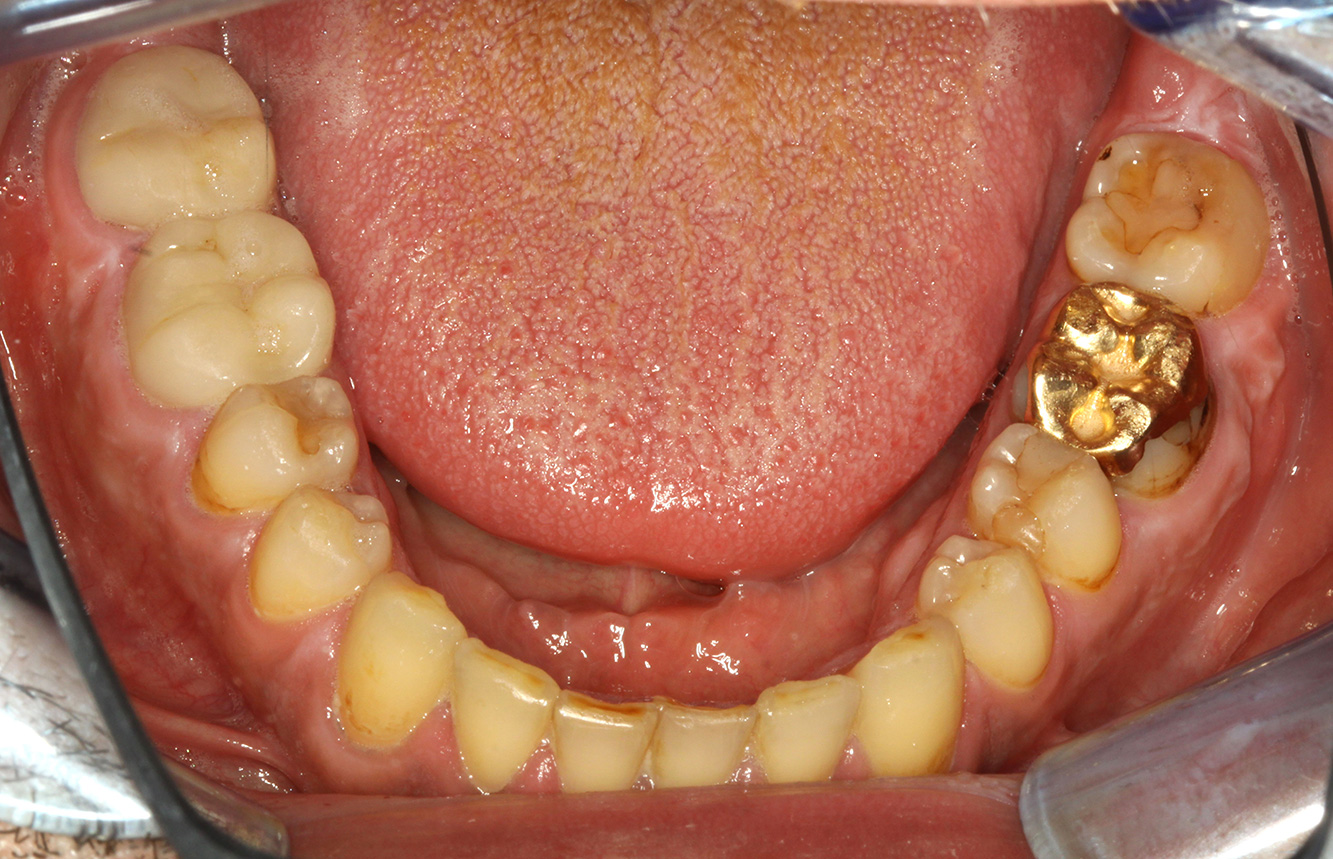

Casi di pazienti secondo l'IPC

I seguenti studi di casi servono a mostrare l'interazione tra i fattori di bisogno e di rischio definiti per l'IPC così come gli effetti dei singoli fattori*.

Il paziente trapiantato con iperplasia gengivale

Si presenta un paziente di 71 anni che ha subito un trapianto di reni e con anamnesi di ipertonia (ipertensione). Considerata la sua storia clinica, serve una terapia a lungo termine con ciclosporina che ha un effetto immunosoppressivo e amlodipina che è specifica contro l'ipertensione. Il paziente riporta anche gengive sensibili e sanguinanti. Per quanto riguarda invece lo stato di salute orale, il paziente ha un restauro, presenta un'iperplasia gengivale marcata, una parodontite allo stadio II, grado B con tasche attive e un'iniziale carie radicolare al dente 22 e in più mancano otto denti. Dalla valutazione del rischio di carie si evince un rischio moderato di carie (API 60). Per la seduta di profilassi si possono formulare i seguenti consigli per il trattamento. di più